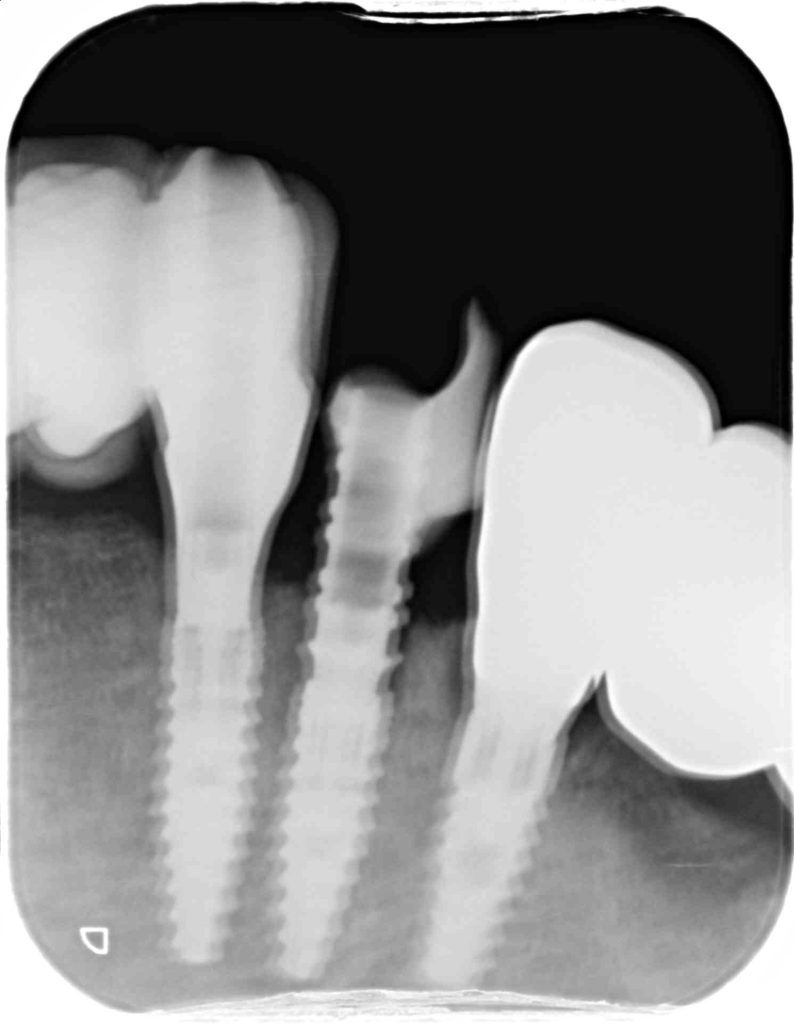

下記のケースは歯周病が原因で犬歯がグラグラしてきました。

犬歯は噛み合わせの中でとても重要な役割があり、側方力を受け止める為に元々歯根が太く、長いです。

今回は抜歯後、すぐに固定式の仮歯を装着し、見た目の不都合が無いようにインプラントに連結をしました。

そのような治療方法を即時荷重と言われます。この治療方法を達成させる為にはインプラント埋入の際に高いトルクを獲得する必要があり、そのために特殊なデザインのインプラントを用います。

抜歯窩に正しいポジションで骨を削合し、しっかり固定をとる事が治療の成否を決めます。

4ヶ月後、最終補綴物であるジルコニア製セラミックをセットいたしました。